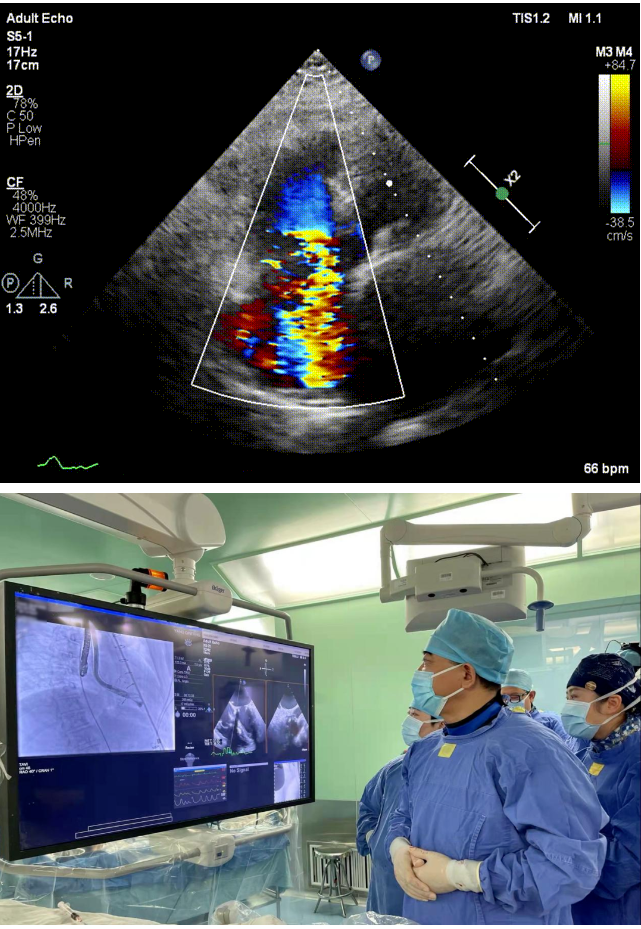

本次接受治療的患者是一名74歲的女性,14年前因風濕性心臟病行二尖瓣生物瓣植入術,合并房顫。近3年來反復因腹脹、納差、下肢水腫入院,藥物治療欠佳。心臟超聲顯示三尖瓣極重度反流(有效反流口面積:0.76cm²,反流容積:79ml),繼發性右房室增大及上、下腔靜脈增寬(右房上下徑*左右徑:52*41mm,右室左右徑:46mm,下腔靜脈:29mm),右室收縮功能正常,肺動脈收縮壓 43mmHg,左心室射血分數73% 。患者既往開胸手術史,術前評估STS 評分為7.02分,CRS 9分,無法接受體外循環下三尖瓣外科手術。面對這一傳統治療無法解決的困境,葛均波院士及其團隊周達新教授、潘文志教授、張源博士、陳莎莎博士及心超室的潘翠珍教授、李偉教授經過討論決定,采用創新的Lux-Valve Plus系統為患者進行經血管三尖瓣置換。

手術在患者全麻狀態下進行,采用經右側頸靜脈作為入路,將裝載有人工瓣膜的輸送器緩慢推送至右心房;并在經食道超聲和DSA的引導下小心調整輸送器角度,將輸送器送入右心室;逐步釋放瓣膜錨定裝置和盤片,調整瓣膜位置后,錨定瓣膜完成植入。術后右房壓明顯下降,從術前的25/10(16) mmHg降至術后即刻的12/7(10) mmHg,術后超聲提示人工三尖瓣同軸性良好,固定牢固,無反流及瓣周漏,手術室即刻拔除氣管插管。